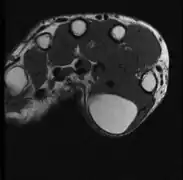

Diagnosis

A physical exam is typically the easiest way to diagnose it. Rarely, a tissue biopsy or imaging may be required. The imaging modality of choice is magnetic resonance imaging (MRI) because it has superior sensitivity of distinguishing it from liposarcoma as well as mapping the surrounding anatomy.[22]